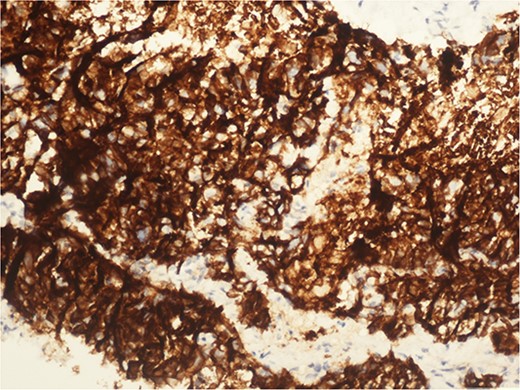

A 59-year-old woman presented with complaints of abdominal pain and abdominal distension for about a month. There was no known systemic disease and no history of previous abdominal surgery. It was learned that the patient had been admitted to the emergency department in another center one month ago with the current complaints and was discharged after medical treatment. Physical examination at the time of admission revealed abdominal distension and diffuse minimal tenderness with no signs of peritoneal irritation. Laboratory tests revealed that hemogram and biochemical parameters were within normal limits, but one of the tumor markers, the patient’s CA 19-9 level was significantly elevated at 855 U/ml (normal range: 0–37 U/ml). Contrast-enhanced CT scan showed a 10×10 cm heterogeneous mass in liver segments 4B-5, extending to segment 6, and free fluid adjacent to the liver and irregular liver contours. Borders of the gallbladder could not be seen. Soft tissues forming nodular mass formation were detected on the omental surfaces (Fig. 1). Computed tomography examination performed at the center where the patient was admitted as an emergency one month ago revealed hypodense lesions measuring 10×8 cm in size in the left lobe of the liver, protruding into the inferior perihepatic area, and 3.5 cm in diameter in segment 5 of the right lobe with no significant contrast enhancement after intravenous injection of contrast material. Perihepatic ascites was not detected and gallbladder size, wall thickness and lumen were normal (Fig. 2). In the light of the radiologic findings, a pre-diagnosis of progressive gallbladder malignancy was considered. The patient was hospitalized in the General Surgery ward for further investigation and treatment. Because of the presence of ascites causing abdominal distension, a percutaneous ascites drainage catheter was placed and 5000 cc ascites drainage was performed. Cytologic examination of the ascitic fluid revealed cell groups with unclear three-dimensional cytonuclear detail among lymphocytes and mesothelial cells with reactive atypia and malignancy was considered suspicious. With the current radiologic and cytologic findings, inoperable metastatic gallbladder carcinoma was considered. Medical treatment was decided by the multidisciplinary oncology council and 18G needle tru-cut biopsy was performed from the 10×10 cm mass adjacent to the gallbladder for definitive tissue diagnosis and adjuvant treatment planning. Histopathologic examination revealed a diagnosis of neuroendocrine carcinoma (NEC) (Fig. 3). Immunohistochemical examination revealed strong staining of tumor cells with CD56 (Fig. 4), synaptophysin (Fig. 5), chromogranin A (Fig. 6), and Ki67 index was >90% (Fig. 7). Weak staining was observed with CK19, CK7, and CDx2, but no staining was observed with CEA and CK20. Morphologic findings were compatible with small cell type. Etoposide and cisplatin chemotherapy was planned but the patient’s general condition deteriorated progressively. The patient couldn’t start chemotherapy and unfortunately resulted in mortality on the 20th day of hospitalization.

The diagnosis of small cell NEC typically involves a combination of clinical evaluation, imaging studies, and histopathological examination. Immunohistochemical staining is crucial for confirming neuroendocrine differentiation, with common markers including synaptophysin, chromogranin A, and CD56. A high Ki-67 index is indicative of the aggressive nature of small cell NEC [2].